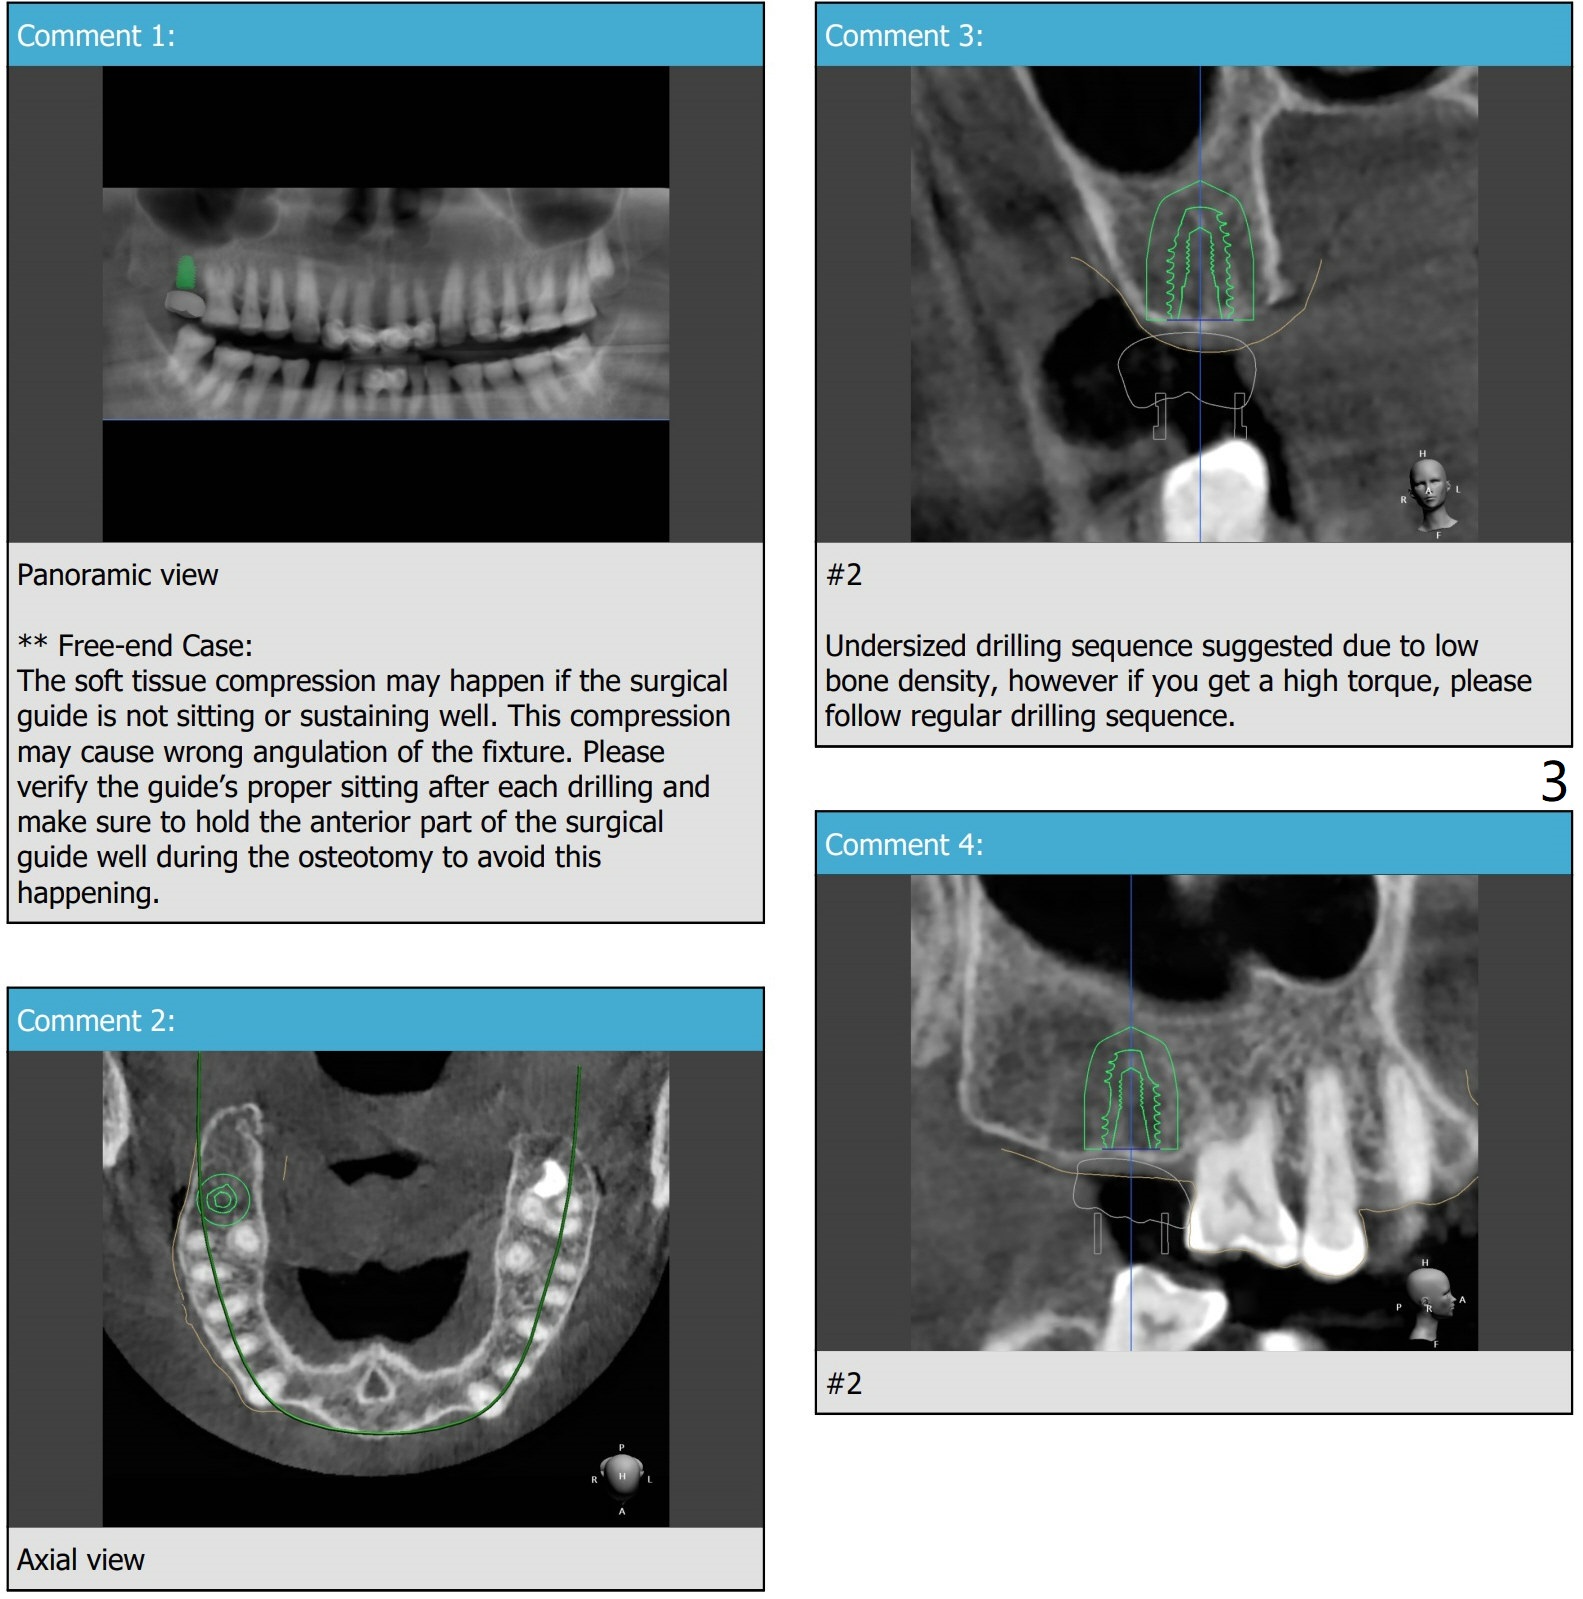

Short Fixture with Low Density

A 70-year-old woman

Return to Protect Graft  Oral Scanner

Xin Wei, DDS, PhD, MS 1st edition 07/17/2021, last revision 07/18/2021